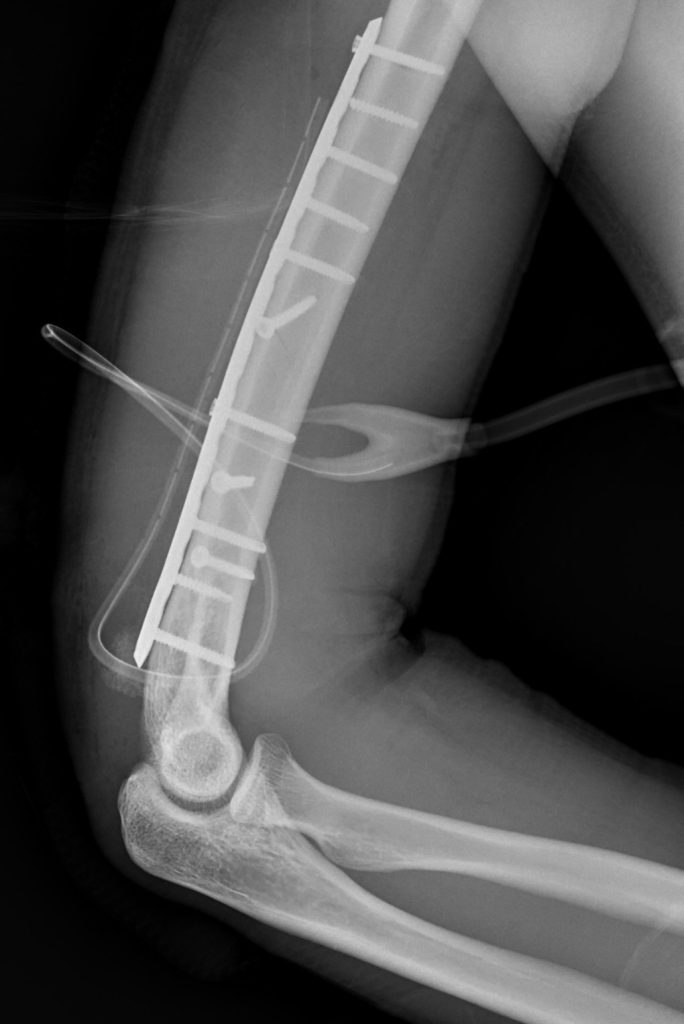

慈濟醫院採取手術方式以鋼板固定,協助骨頭穩定癒合。(花蓮慈濟醫院提供)

慈濟醫院表示,醫療團隊採取手術方式,自後側切入,在避開神經前提下進行骨折復位,並以鋼板固定,協助骨頭穩定癒合,經適當治療與復健,多數病人可恢復正常生活與活動能力。